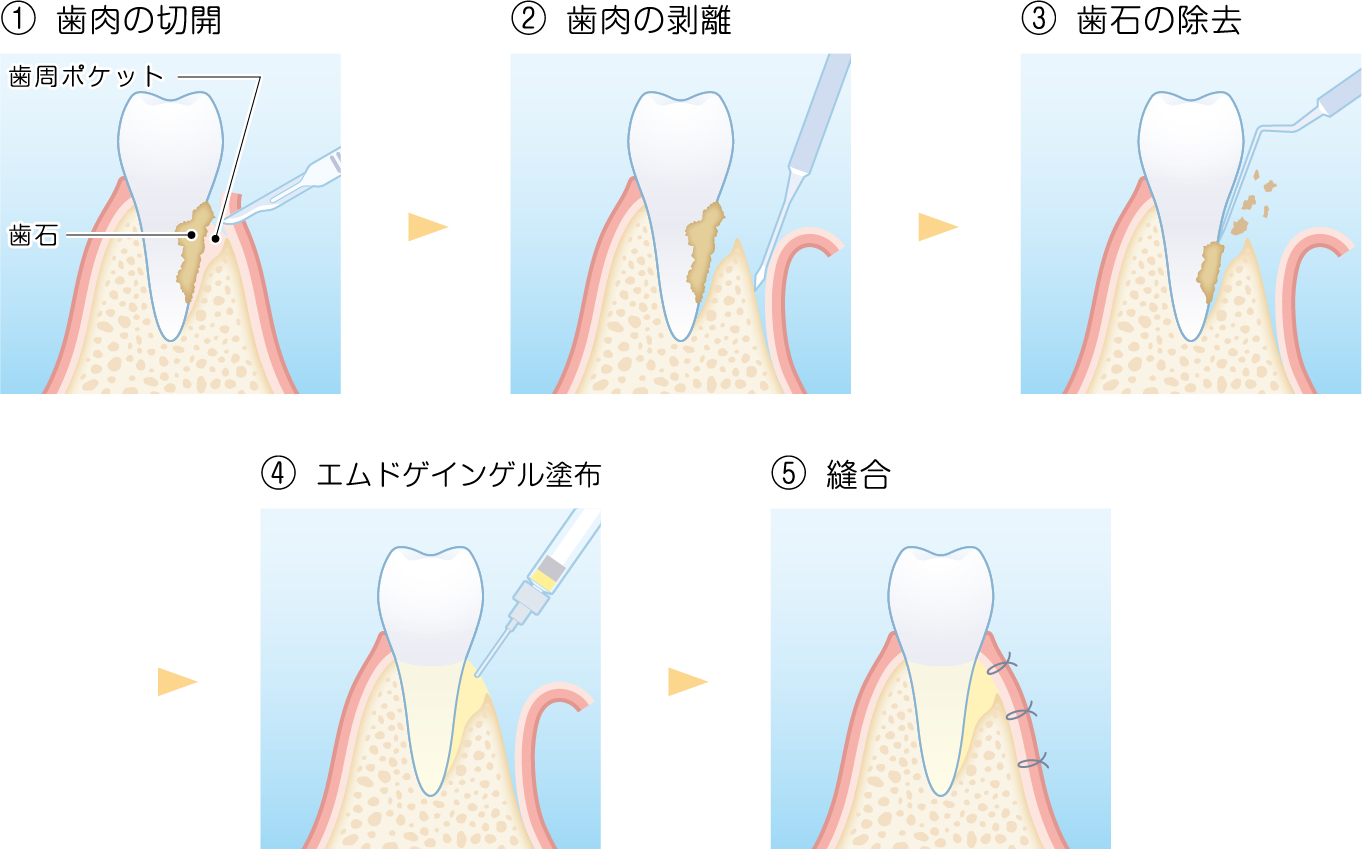

エムドゲインゲルの主成分は、「エナメルマトリックスデリバティブ」と呼ばれる豚の歯胚組織からつくられたタンパク質の一種です。世界各国で使用されており、2002年に厚生労働省から認可を受けた安全な生体材料です。

これは、特殊なたんぱく質製剤(エムドゲイン®など)や人工骨を用いて、溶けてしまった骨や歯周組織を再生させる先進的な治療法です。